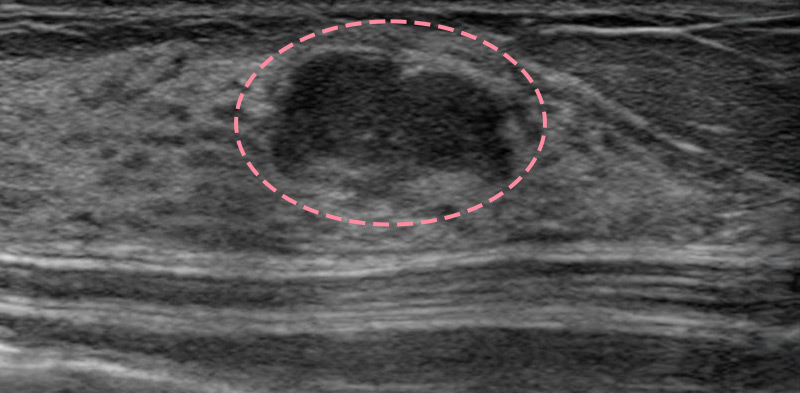

보형물 가슴성형 후 제법 크기가 있는 종양이 발견된 사례입니다.

가슴성형 후 맘모톰시술은 보형물의 위치를 파악하면서 바늘을 다루어야 하기 때문에 고도의 숙련도와 정밀한 판독 능력이 필요합니다.

한송이 원장은 다양한 사례를 접해온 경험과 전문성을 바탕으로 시술을 성공적으로 마쳤습니다.

총조직검사 후 최종 진단 결과 양성 종양(섬유선종)으로 확인되어 맘모톰 시술로 제거를 진행했습니다. 7개월 경과 후 검사를 통해 인공 보형물의 누수 및 파손 없이 깨끗한 내부 상태가 확인되었습니다.